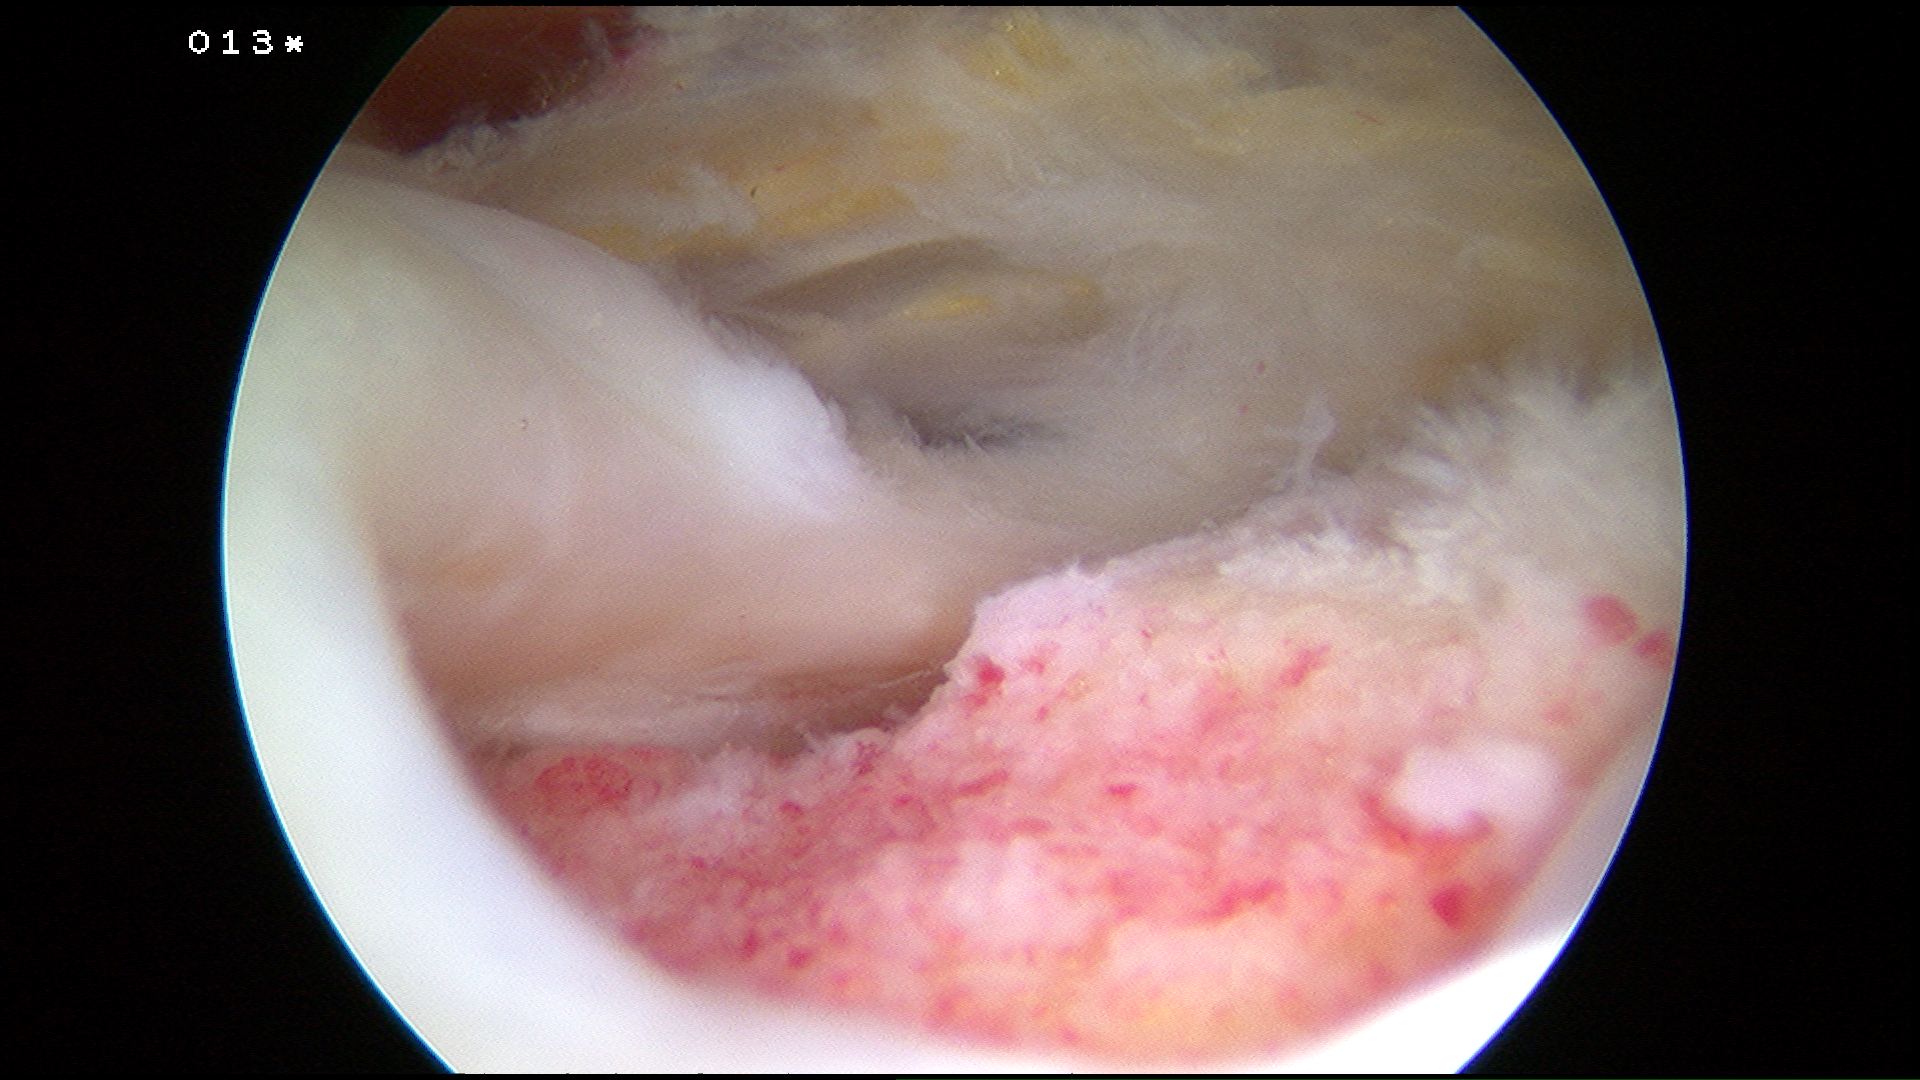

- perform bursectomy +++ for visulisation

- bursa posteriorly and medially often bleeds

- perform SAD

- control bleeding with electrocautery and temporary increases in pump pressure

Preparation

Prepare insertion

- debride tendon edges

- debride footprint to punctate bleeding